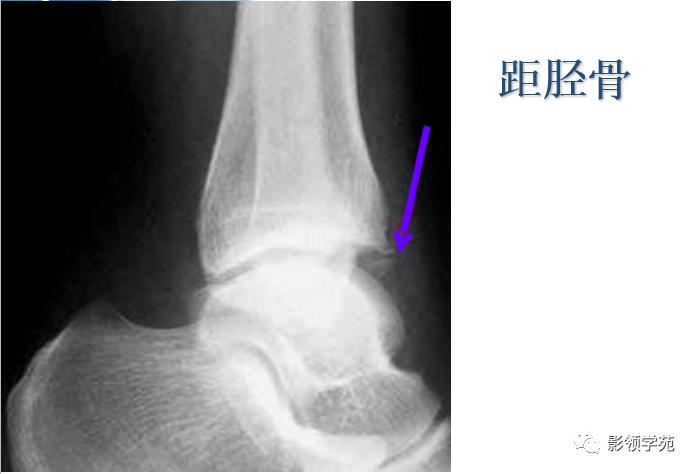

三角骨

三角骨是常见的变异,也被误称为距骨副骨。呈三角形, 与距骨后缘相切,三角骨与距骨后突外侧结节腓侧隐窝相对应。

-

三角骨可以成对存在,还可以与外侧结节融合,形成单一的突起,并可与距骨融合或形成关节。

三角骨与其它副骨一样,可妨碍足的运动,同时本身亦可受外界影响发生无菌性坏死。

正常变异:距骨三角骨